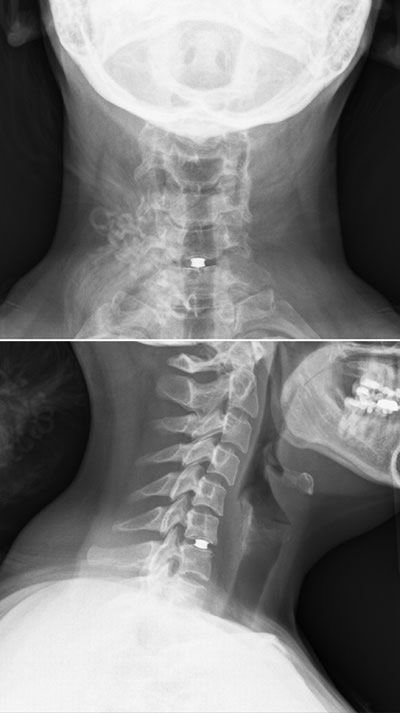

Van Kort's herniated disc causing debilitating pain.

Van Kort had a herniated disk between C6 and C7. With the severity of the pain and weakness, Dr. Jenkins quickly worked her into his surgery schedule. Weeks prior to relocating to a new city, she was relieved after meeting Dr. Jenkins. She knew she had a trusted surgeon on her side and didn’t have to search blindly in a new city for someone she could trust to do her spine surgery.

“Elizabeth presented with a problem called myeloradiculopathy from a cervical disc herniation,” said Dr. Jenkins. “This is where a disc herniation in the neck can put pressure on the spinal nerve (causing pain) and spinal cord (causing neurologic dysfunction). The unique thing about Elizabeth is how young and healthy she was at the time of presentation. She did not have a lot of arthritis or bone spurs. Therefore doing the typical spinal fusion was not a great option for her. Following FDA trial indications for cervical disc replacement, Elizabeth was a perfect candidate for a cervical disc replacement. This allowed me to solve her spinal cord and nerve root compression without fusion of her spine and preserving motion.”